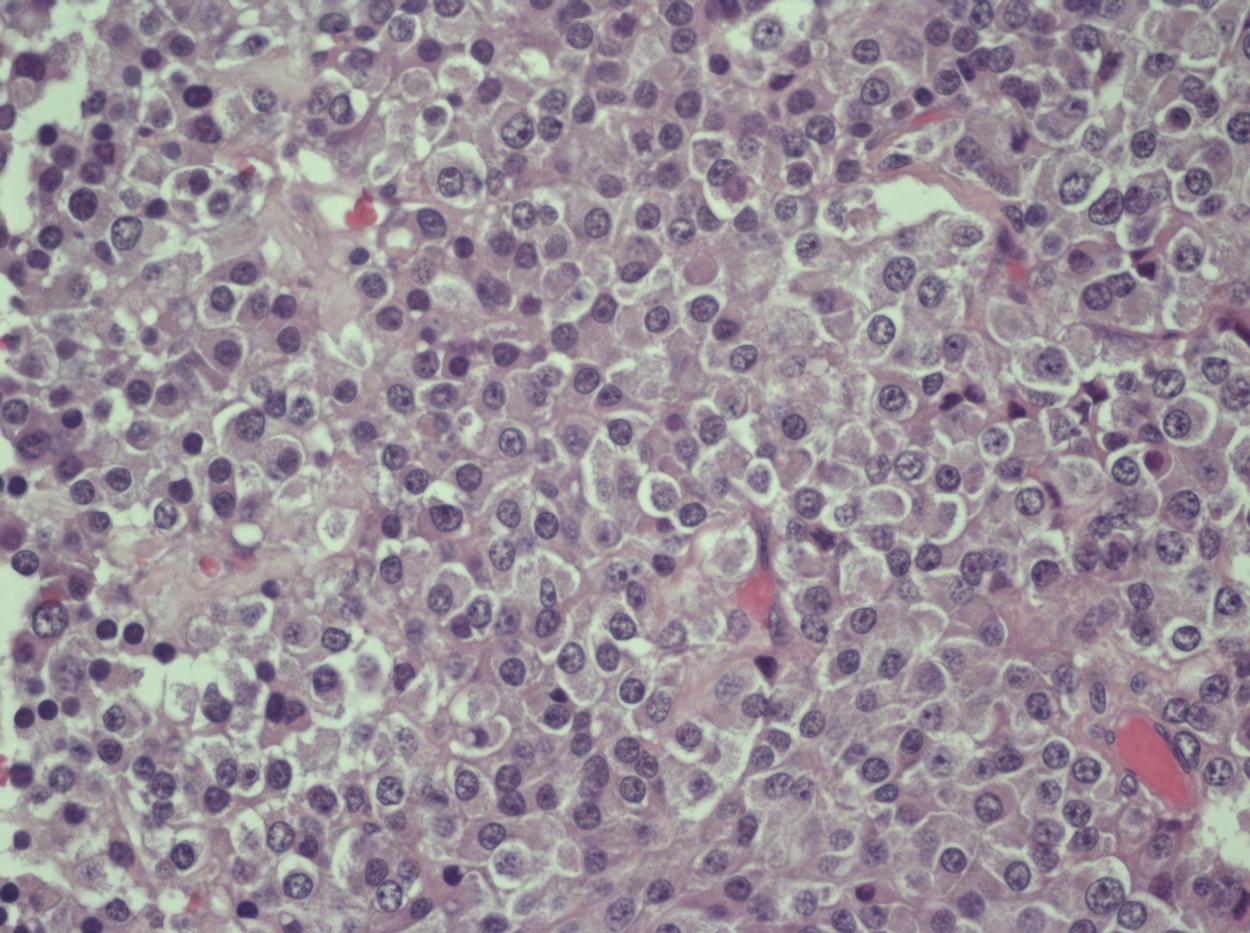

При морфологической оценке удаленного материала было выявлено 26 аденом гипофиза (рис. 1, на цв. вклейке), в 13 случаях мы наблюдали сочетание аденомы c гиперплазией аденогипофиза. Клеточный состав образований был представлен в 23 случаях базофильными клетками, в 11 — эозинофильными клетками, в 3 — состоял из эозинофильно-хромофобных клеток, в 2 — из базофильно-эозинофильных. Не было выявлено разницы между группами по клеточному составу и характеру новообразований (p>0,05). Пролиферативная активность в обеих группах была преимущественно низкой. Лишь в 3 образцах индекс пролиферации превышал 2% и был равен 3, 4 и 15%, соответственно.

В обеих группах подсчитывали количество кровеносных сосудов с оценкой их диаметра (рис. 2—4, на цв. вклейке).

4. Аденома | |

| Тема | ||

| Тип | Исследовательские инструменты | |

Посмотреть

(3MB)

|

Метаданные ▾ | |